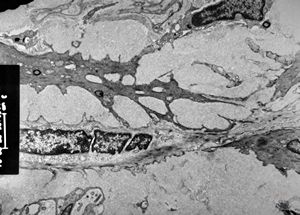

M,60y. | jejunum - amyloidosis

M,60y. | jejunum - amyloidosis(semithin section)